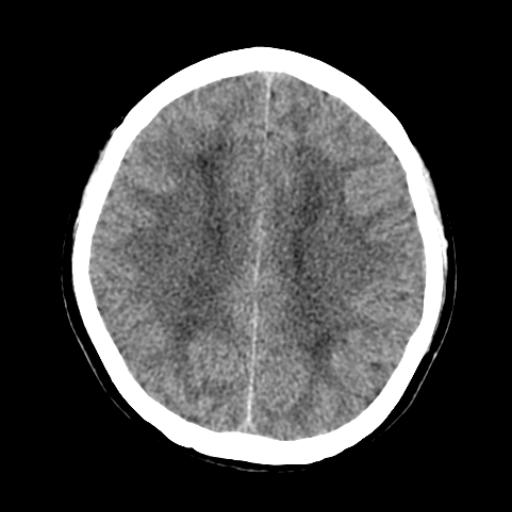

40f头晕十多天,右上肢麻木一天

脑白质变性或ms

脑白质脱髓鞘改变。

脑白质病;建议行mri检查。